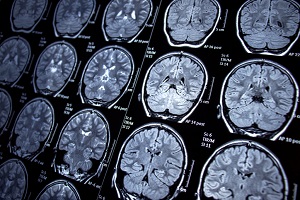

Frontotemporal dementia occurs in parts of the brain that control behavior, personality, and language. Many symptoms may result from frontotemporal dementia, such as unusual behaviors, emotional problems, trouble communicating, difficulty with work, or difficulty with walking. FTD is rare and tends to occur at a younger age than other forms of dementia. Roughly 60% of people with FTD are 45 to 64 years old, according to the National Institute on Aging (NIA).